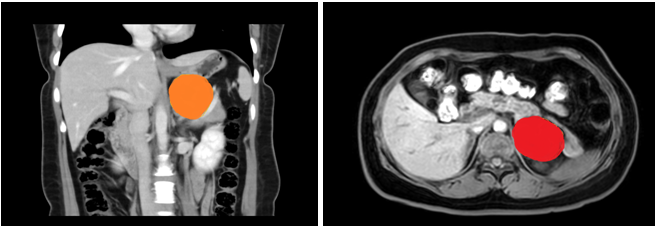

患者,女性,35岁,在欧美视频 上腹部CT增强示:左侧腹膜后囊性病变,支气管囊肿不除外;入院后上腹部MRI平扫+DWI+增强扫描+MRCP示:左侧肾上腺上方囊性病变,考虑来源腹膜后间隙,1)支气管源性囊肿2)淋巴管囊肿可能,建议复查。

在张煜副主任带领下,经过肝胆外科全科细致讨论,认为占位较大,位置靠后,微创难度大,需完善相关检查,精细术前准备。经过医护一体化管理,打消了患者的术前顾虑,在全麻下行腹腔镜下腹膜后囊性占位手术+广泛腹腔粘连松解术,手术顺利,术后病理结果为良性,患者术后一周内顺利出院。患者表示,术后经过了解,得知此例手术难度较大,目前恢复良好,特意送来锦旗表达感谢。